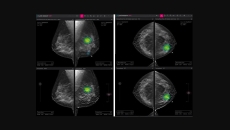

The company develops AI tools to analyse chest x-rays and breast mammography.

The diagnostic software runs on Lunit's AI technology to spot major abnormal findings.